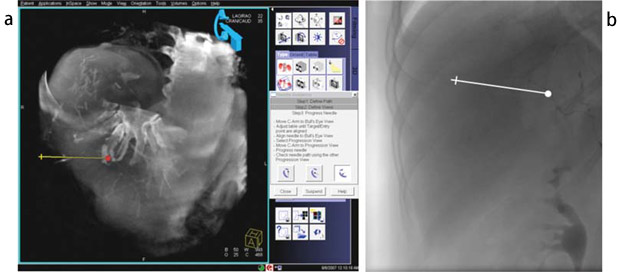

syngo iGuide(オプション)は,主に腹部の非血管系IVRにおいて各種デバイスの誘導を支援するツールである。DynaCT画像上でパスを設定でき,作成パスを透視画像上に投影表示できる(図4)。

図4 syngo iGuide

三次元画像上(a)で計画したパスが透視画像上(b)に投影され,術者のデバイス誘導を支援する。多軸アームとの併用により,適用可能な領域が広がる。 |